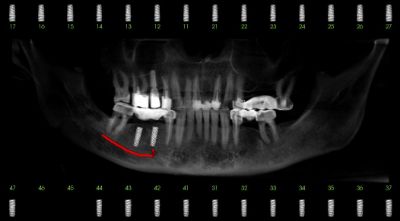

Этап 1. Подготовка

На этапе подготовки к реализации протокола  вам сделают общие анализы крови, а также конусно-лучевую томографию (КЛКТ), которая необходима для определения оптимальных мест для размещения имплантов в челюсти. На основе снимка КЛКТ в специальной программе вам составят цифровой диагностический план вашего лечения.

Иплантация на 4-х опорах выделяется необычной установкой искусственных корней по углом до 45 градусов. Такая постановка позволяет удлинять протеза до 12-14 зубов, в то время как при классической имплантации их всего 10. В тоже время, уменьшается само хирургическое вмешательство, так как 8-10 имплантов заменяются всего 4.